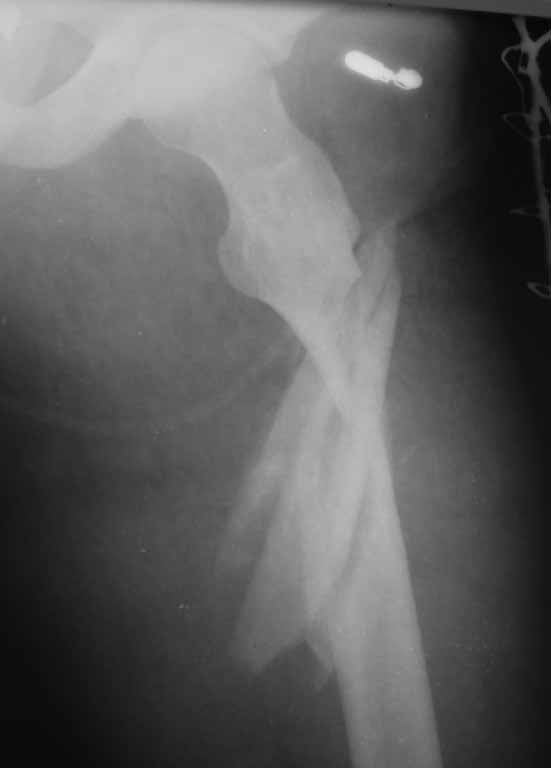

[Ortho] подвертельный перелом - тактика лечения?

Ваши предложения по тактике лечения, планируется закрытая репозиция, ИМОС AFN, кто встречался с подобным, какие могут быть сложности интраоперационно